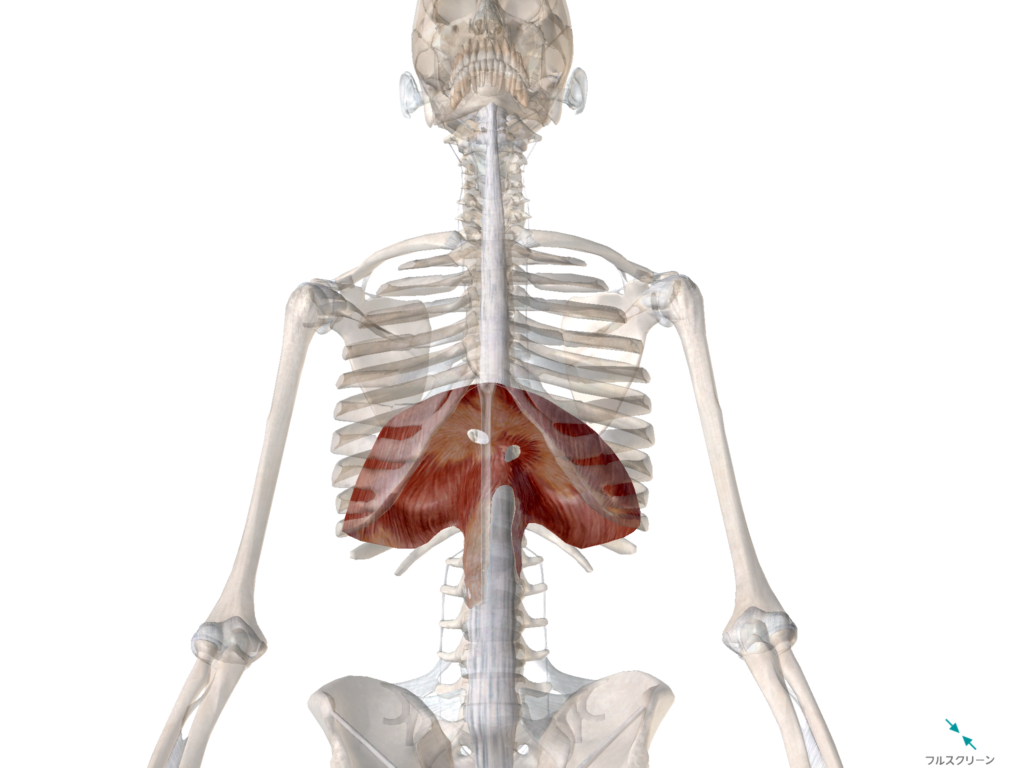

横隔膜はこちら

肺の真下にある、赤いやつが『横隔膜』ですね。

この東京ドームの屋根部分みたいなやつが、東京ドームの屋根がしぼむかのように下の方に下がっていくと、空気が入ります。

イメージがしにくいかもしれませんが、イメージではこんなかんじです。↓

※黄色が横隔膜

※赤が肺

↑このように、横隔膜が引き下がれば勝手に肺に空気が入るようになっています。